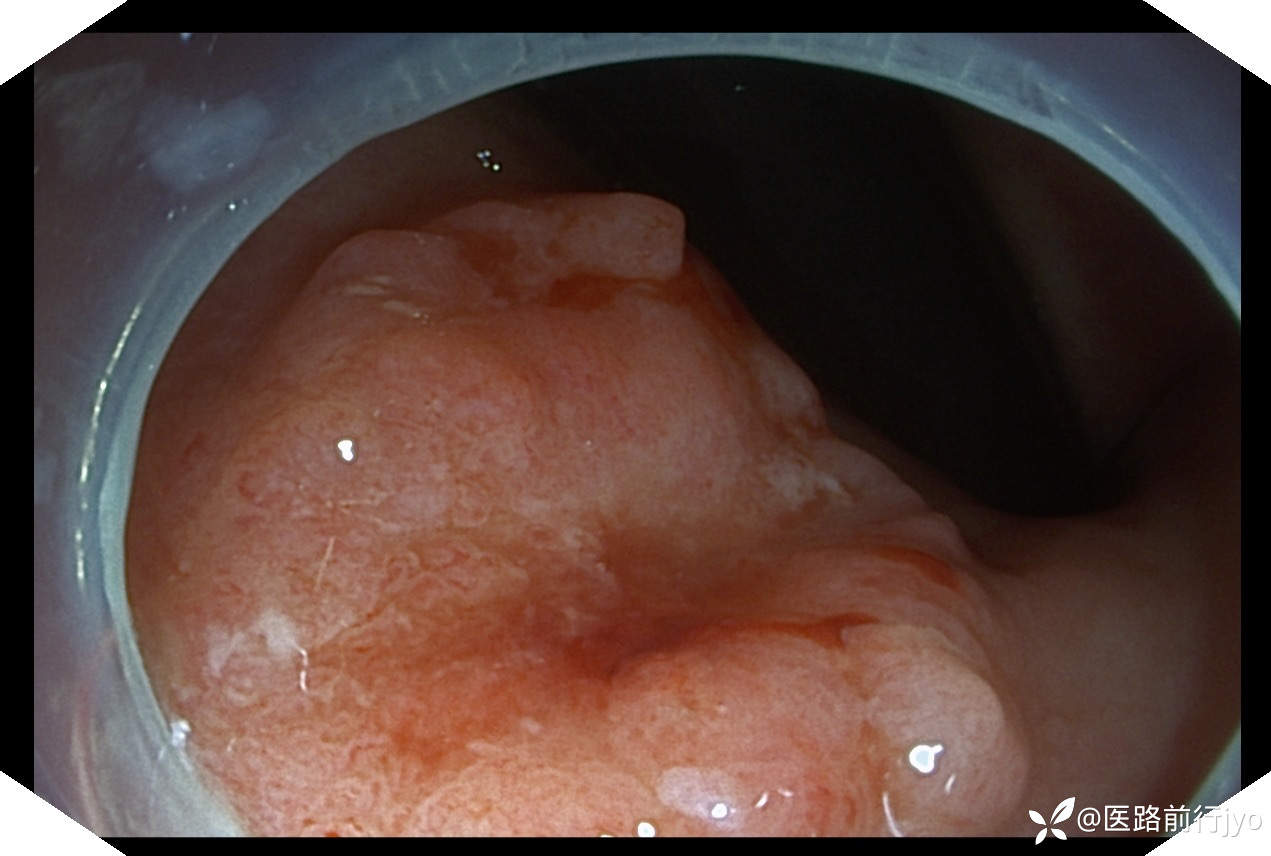

今日上午一例肠镜:患者 女 67岁 患者肠道清洁好,乙状结肠仅发现1枚小息肉,本准备退镜收工,退镜到肛门口突然看到一隆起性小片粘膜,立即倒镜观察考虑直肠早期癌变,距肛周约1cm的大小约1.6cmx1.3cm椭圆形欠规则隆起,中央凹陷伴自发性出血,活捡5块,质脆,易出血。考虑诊断:直肠粘膜不规则(11a+11c)隆起(考虑直肠癌可能)